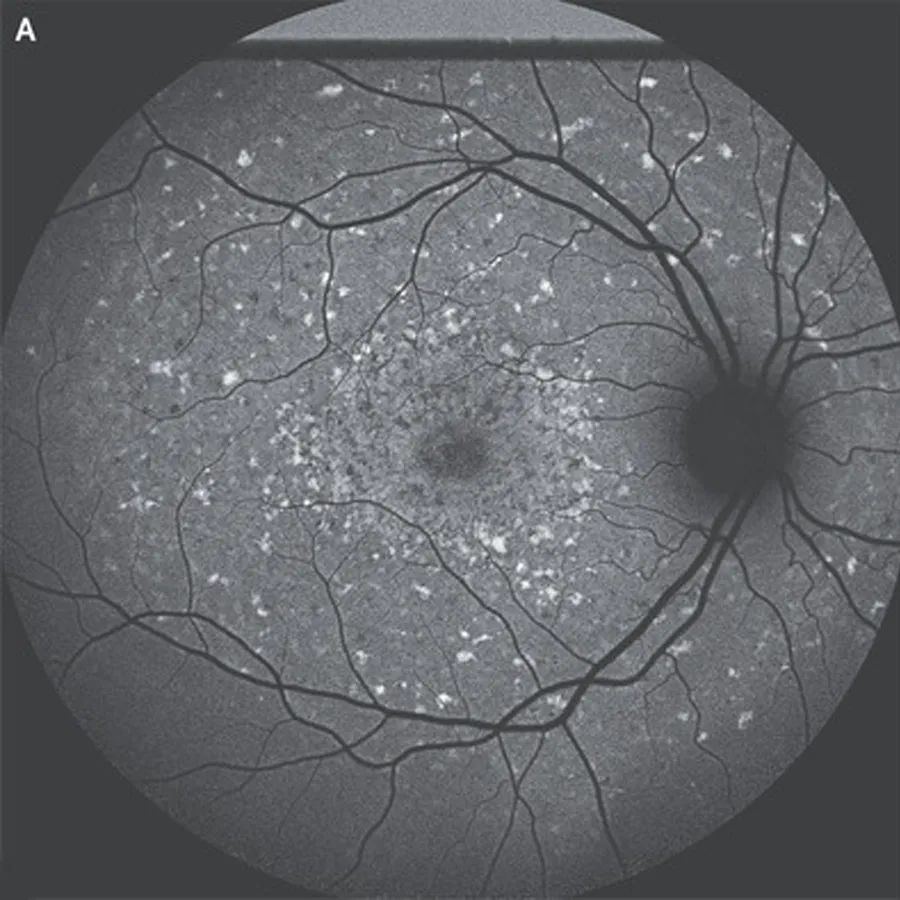

双眼眼底检查显示广泛的黄色斑点。

短波长自体荧光显像显示弥漫性高自体荧光病变,提示双视黄醇积聚,视网膜色素上皮中央区域呈斑片状萎缩,视盘周围未见病变。